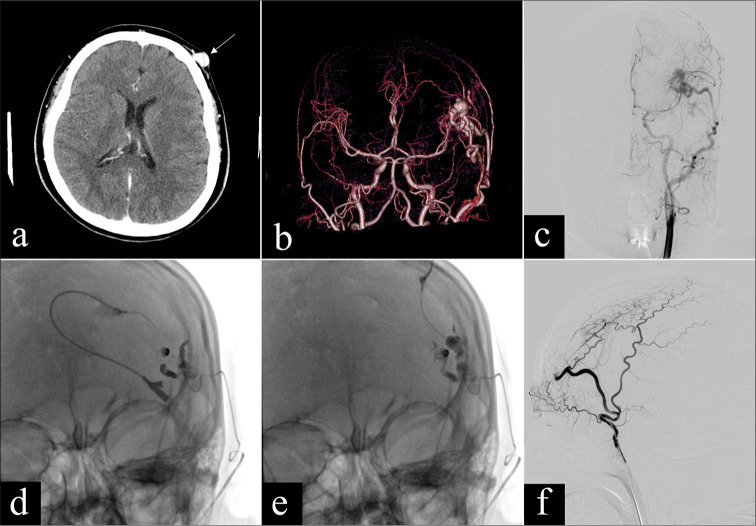

Objectives: Congenital arteriovenous malformations (AVMs) are characterized by abnormal connections between arteries and veins, often presenting challenges in treatment due to their complex vascular structure. Endovascular therapies, including embolization techniques, have become integral in managing AVMs, yet optimal treatment strategies remain under investigation. This retrospective study aimed to evaluate the safety and efficacy of percutaneous glue embolization of n-butyl cyanoacrylate (nBCA) combined with arterial embolization in treating extracranial AVMs.

Material and methods: This retrospective study included 11 patients with extracranial AVMs who underwent percutaneous injection of nBCA glue embolization combined with arterial embolization at our institution between May 2015 and October 2023. Angiographic classification was performed using the Cho-Do vascular imaging system and the Schobinger classification system to categorize the AVMs. Treatment efficacy was assessed based on the percentage of vessel occlusion observed in angiography or imaging studies. The occurrence of major and minor complications was also evaluated.

Results: Eleven patients received 16 treatments, involving a combination of arterial and percutaneous embolization techniques. Five cases achieved complete recovery, while four cases showed significant improvement, resulting in an overall treatment success rate of 81.8%. Favorable outcomes were observed in terms of symptom alleviation and lesion occlusion. Adverse events were minimal, with transient pain and edema being the most common postoperative complaints. Only one case of mild post-operative complication occurred.

Conclusion: Percutaneous glue embolization combined with arterial embolization proves to be a safe and effective treatment modality for extracranial AVMs, with acceptable rates of complications and favorable treatment outcomes.